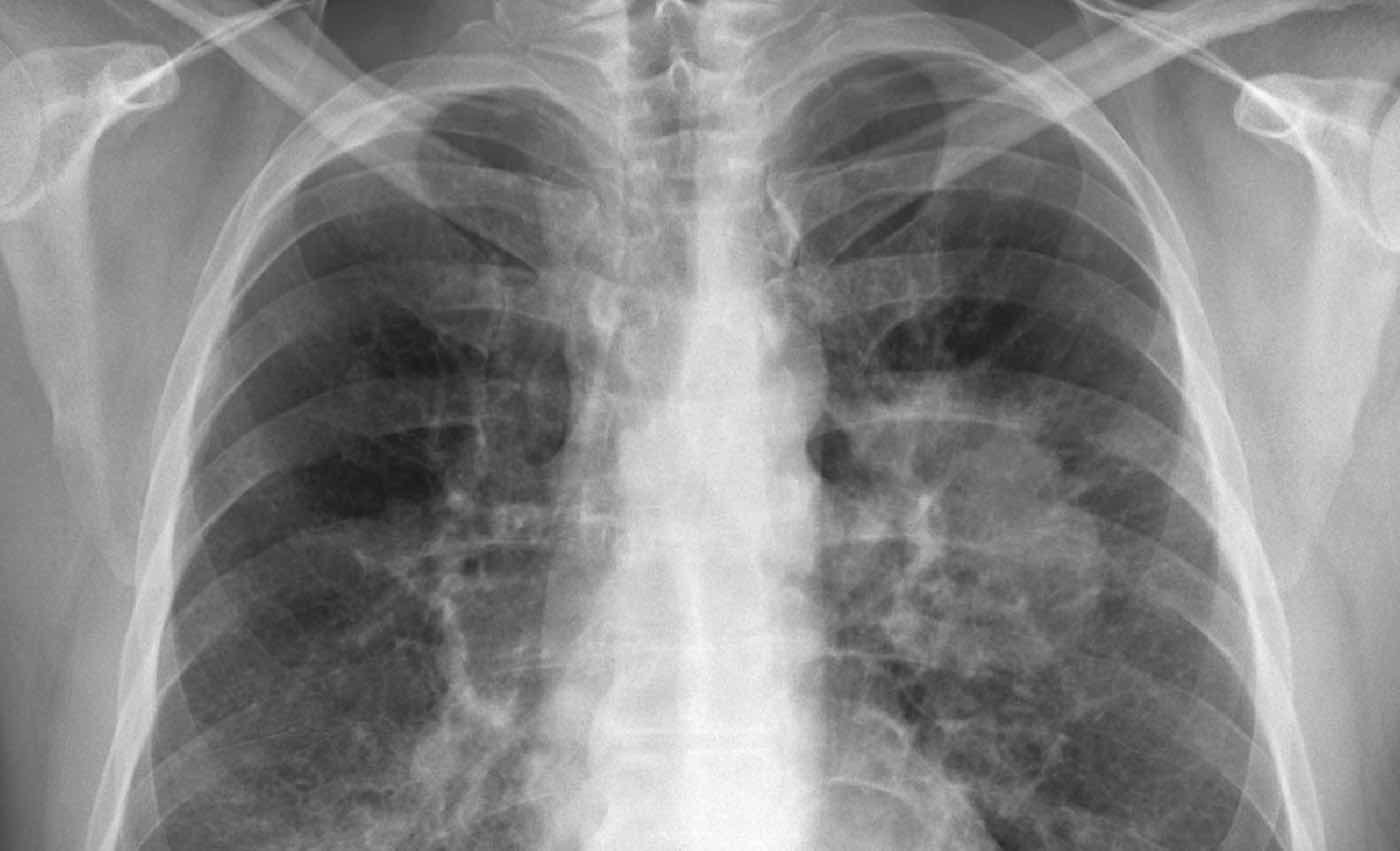

The patient, who was in his mid-40s, was hospitalized after a tumor in his left lung blocked the main artery, leading to its collapse. Upon admittance to the Rabin Medical Centre in Petah Tikva, doctors originally thought that his lung would need to be re-sectioned while he embarked upon the dangerous road of waiting for a transplant.

During the operation, the man continued to breathe out of his good lung while his other was disconnected, cleansed from the tumor, and reconnected after inflating it as a way of making certain it was still working and the tissue was still healthy.